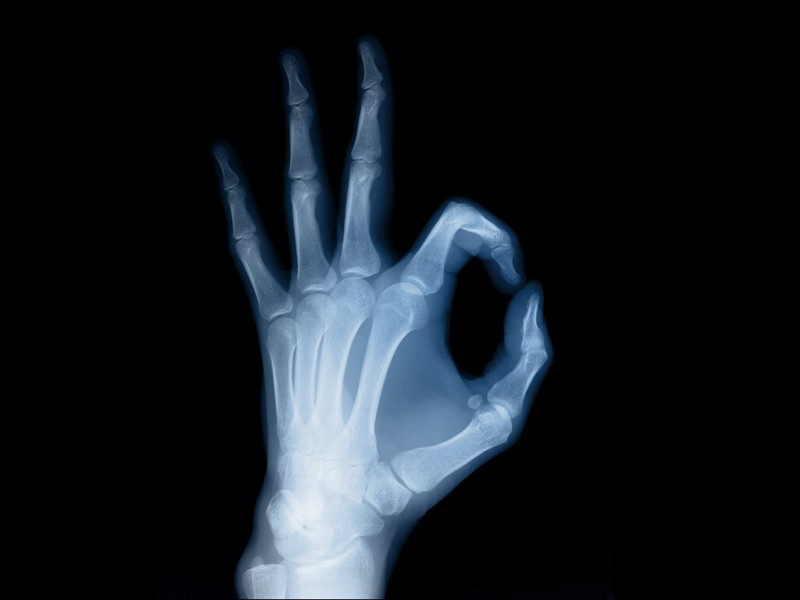

X光、CT、B超、核磁共振……这些都是医疗中常用的影像学检查法,但是它们有什么区别,看什么病应该照什么影像呢?